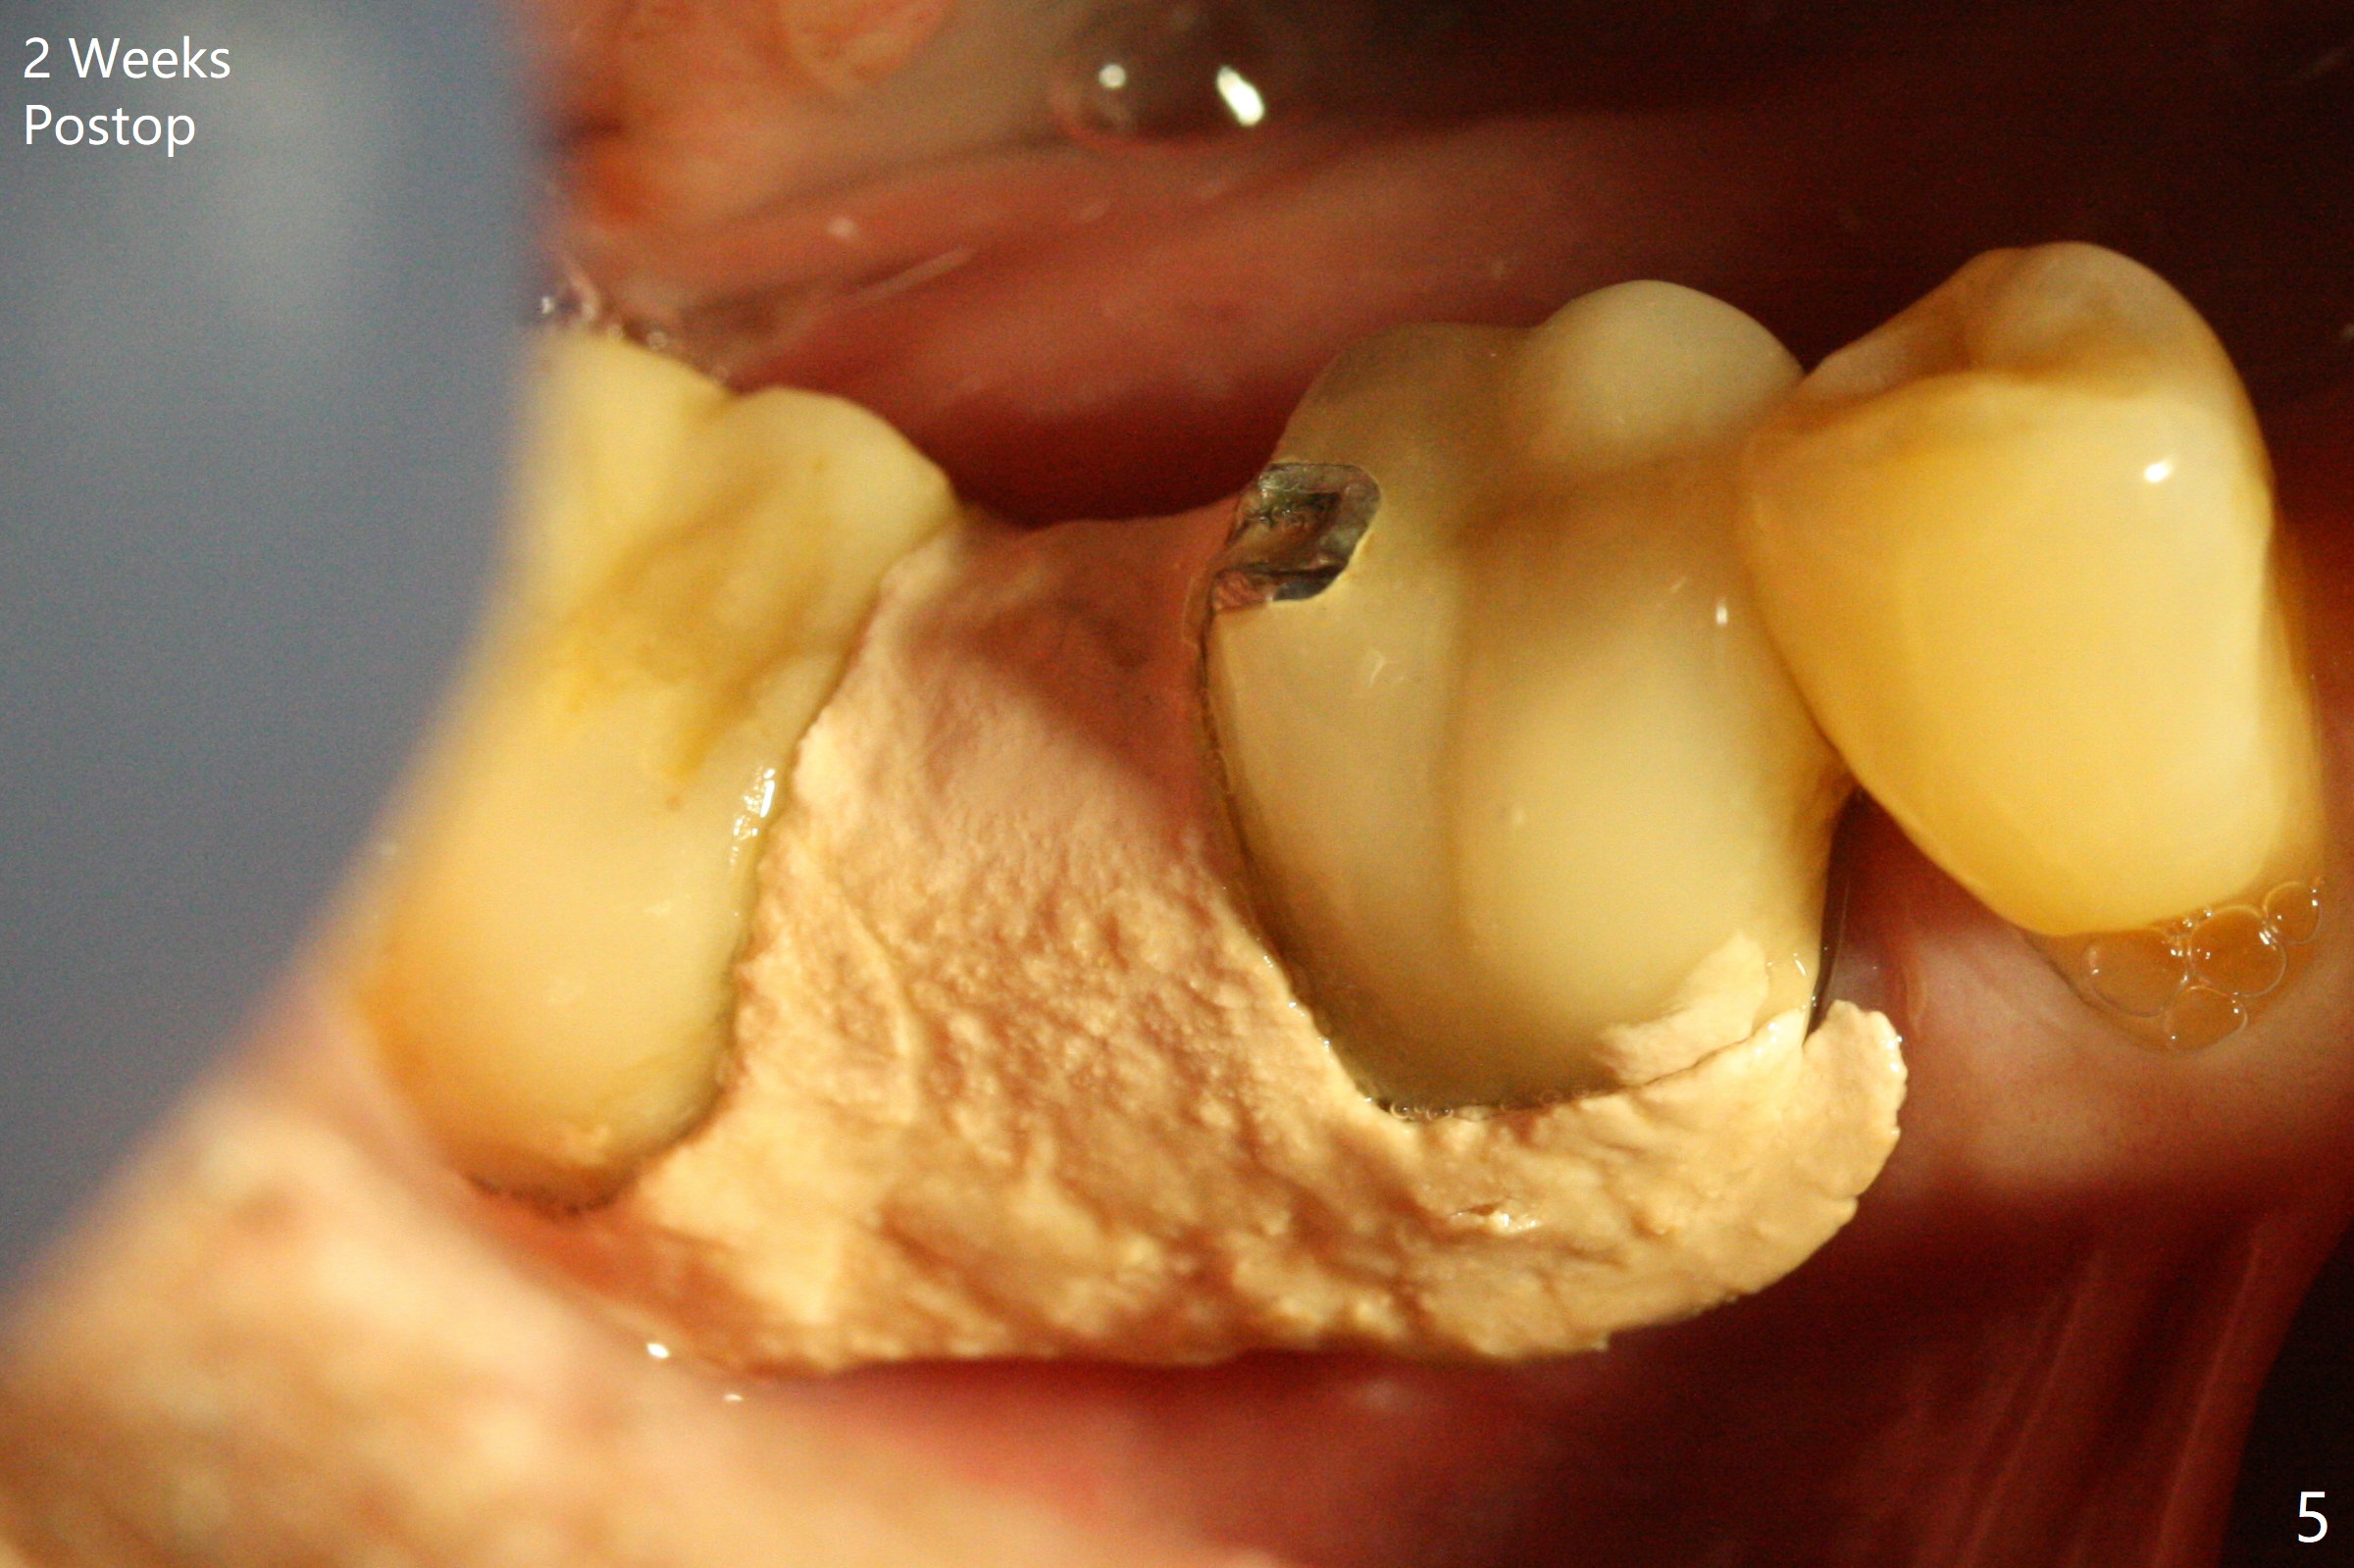

There is a space underneath the pontic at #30 (Fig.1 *), the basis for food impaction. After sectioning between the pontic and the posterior retainer, the pontic is removed from the anterior retainer with an attachment (Fig.2 *). The initial depth of osteotomy is 10 mm following ridge top reduction (Fig.3). A 3x10(4) mm 1-piece implant is placed with >50 Ncm; to reduce possibility of crown dislodgement from the implant, the retainers will be kept with modification of the proximal surfaces as shown by curved lines in Fig.4. Periodontal dressing is applied after suturing. There is no postop paresthesia. The periodontal dressing remains in place 2 weeks postop because of engagement into the attachment slot and undercuts (Fig.5). The patient returns 3 months postop; after minor contour adjustment (Fig.6 red curved line), impression is taken. The permanent crown is temporarily cemented (3.5 months postop) in case of food impaction due to the distal overhang of the tooth #29 (Fig.7). In fact the patient returns 4.5 months post cementation with right TMD (muscle relaxant prescribed) and food impaction, although there is no bone resorption (Fig.8,9). It appears that the crown at #29 needs to be redone, while porcelain will be added to the mesial surface of the one at #30 (Fig.10 red lines). In fact the crown at #30 is redone because of loose proximal contact with #31; there is no bone resorption 13 months post cementation (Fig.11). Bone resorption remains unnoticeable 28 months post cementation (Fig.12,13).